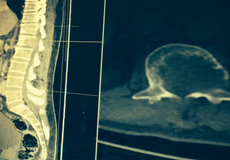

ونظراً لأنها من الحالات النادرة، فقد قام الفريق الطبي بإجراء فحوصات دقيقة لمعرفة سبب الضغط على الحبل الشوكي بالإضافه الى أخذ عينة بالتوجيه الإشعاعي والتي أظهرت نوعية الورم وسلوكه الطبي الذي يتطلب إجراء اقفال للأوعيه الدمويه المغذيه للورم قبل إجراء العملية الجراحية لاستئصاله وذلك لكثافة الأورده والشرايين بداخل الورم، الأمر الذي قد ينتج عنه نزيف حاد أثناء التدخل الجراحي والذي قد يؤدي إلى وفاة المريض لاقدر الله أثناء العمليه الجراحيه.

وقد اوضح الفريق الطبي برئاسة الدكتور محمد خشاب وعضوية كلا من الدكتور حاتم الشريف و محمد خليفه أن هذا النوع من الأورام عادة ما يسبب آلام شديده بالظهر وقد يصاحبه أعراض شلل جزئي أو كامل بالاطراف وذلك نتيجة انتشار الورم بالقناة العصبيه والذي بدوره يسبب ضغطاً شديداً على الحبل الشوكي والأعصاب. وقد استطاع الدكتور فواز الشريف و الدكتور تركي الحازمي من قسم الأشعه التداخليه بالمستشفي اقفال الأورده والشرايين بمنطقة الورم للحد من شدة النزيف أثناء التدخل الجراحي.

وبين الدكتور محمد خشاب أن العملية كانت معقدة، واستغرقت "9" ساعة تم خلالها إجراء تحرير للحبل الشوكي و الأعصاب واستئصال الورم ووضع دعامه أماميه لتحل مكان الفقره المتأثره بالورم مع التثبيت وذلك عن طريق إجراء فتحه واحده من الخلف فقط.